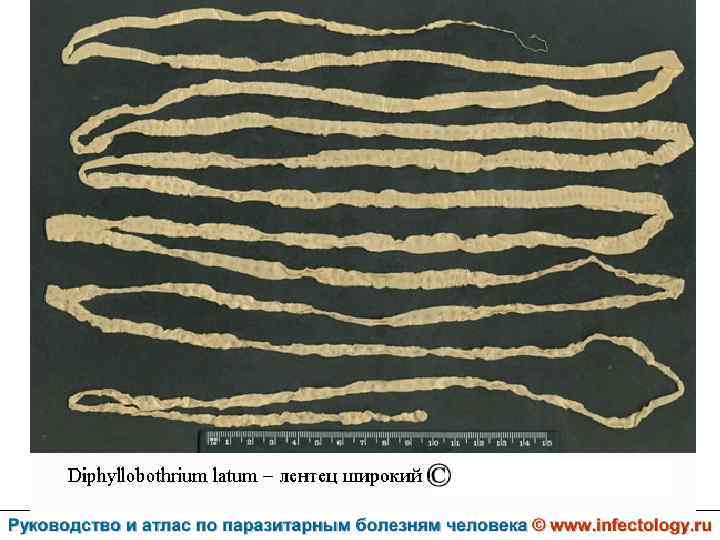

Дифиллоботриоз (шифр по МКБ 10 – B 70. 0) – зоонозный биогельминтоз с хроническим течением, характеризующийся нарушением функций верхнего отдела пищеварительного тракта, а при тяжелом течении - развитием анемии.